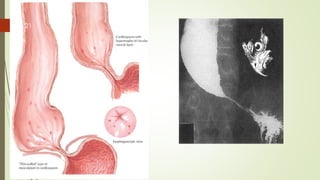

Lower oesophageal sphincter usually prevents

reflux by the following mechanisms:

a physiological high-pressure zone (not a true

sphincter) in the lower end of the oesophagus

the mucosal rosette at the cardia, which acts like a plug

the angle at which the oesophagus joins the stomach

between the left border of the oesophagus and the

fundus (angle of His)

the diaphragmatic sling (crura), which acts like a

pinchcock at the lower end of the oesophagus

the high-pressure area at the lower end of the

oesophagus, caused by the positive intra-abdominal

pressure.